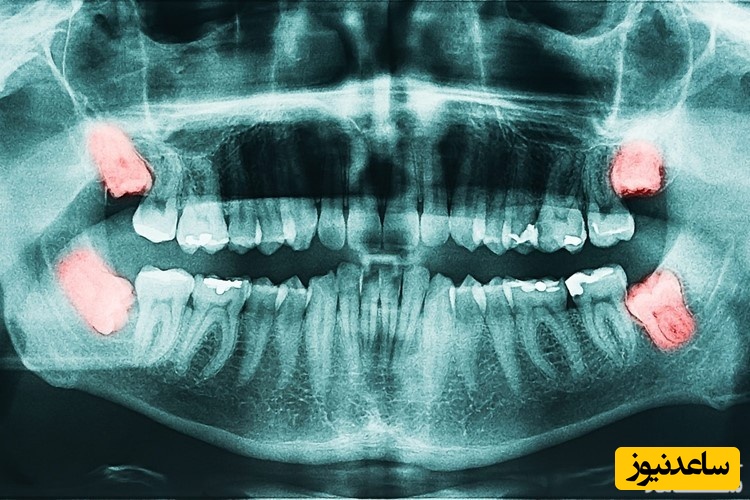

عصب کشی دندان حتماً به عکس رادیوگرافی نیاز دارد پس از مشاهده آن توسط دندانپزشک متخصص کودکان دندان موردنظر بی حس می گردد و پوسیدگی ها برداشته می شوند اگر التهاب محدود به تاج دندان باشد پس از خارج کردن عصب تاج دندان خمیرهای مخصوصی داخل دندان قرار داده خواهد شد و سپس دندان شیری ترمیم و روکش می گردد. اگر التهاب ریشه دندان را درگیر کرده باشد باید عصب ریشه دندان با وسایل مخصوصی خارج گردد و داخل ریشه و تاج دندان شیری با خمیرهای مخصوصی پر شود و سپس دندان شیری ترمیم یا روکش گردد.

بله! پوسیدگی دندان شیری ممکن است به سرعت پیشرفت کرده و ناحیه عصب دندان شیری را درگیر نماید. حتی ممکن است پوسیدگی هایی که به نظر والدین بسیار کوچک و سطحی باشند پس از معاینه توسط دندانپزشک متخصص کودکان و تهیه رادیوگرافی های موردنیاز مشخص گردد که نیازمند درمان عصب کشی می باشند حتی اگر کودک دردی را تجربه نکرده باشد. گاهی در مواردی پوسیدگی وقتی توجه والدین را جلب می کند که دندان دچار آبسه مزمن شده است و والدین با کمال تعجب اظهار می کنند که کودک هیچ وقت از درد شکایت نکرده بود.قابل ذکر است که در برخی موارد نیز ممکن است پوسیدگی ها از همان ابتدای شروع پوسیدگی با درد همراه باشند و وقتی التهاب به ناحیه عصب دندان شیری می رسد کودک دچار درد شدیدتری گردد. بنابراین صرفاً نداشتن درد معیار درگیر نبودن عصب دندان نیست و باید دندان توسط دندانپزشک متخصص کودکان معاینه گردیده و با رادیوگرافی های مناسب کنترل گردد.

خیر، مراحل عصب کشی دندان شیری معمولاً ساده تر از مراحل عصب کشی دندان دائمی بزرگ سالان است. درصورتی که التهاب در مراحل اولیه باشد صرفاً عصب تاج دندان خارج می گردد و درصورتی که التهاب گسترش یافته باشد و فضای عصب داخل ریشه دندان شیری را نیز درگیر کرده باشد عصب داخل ریشه دندان نیز خارج می گردد. برش مقطعی از دندان دائمی که در بالا و پایین دندان های شیری قرار دارند.